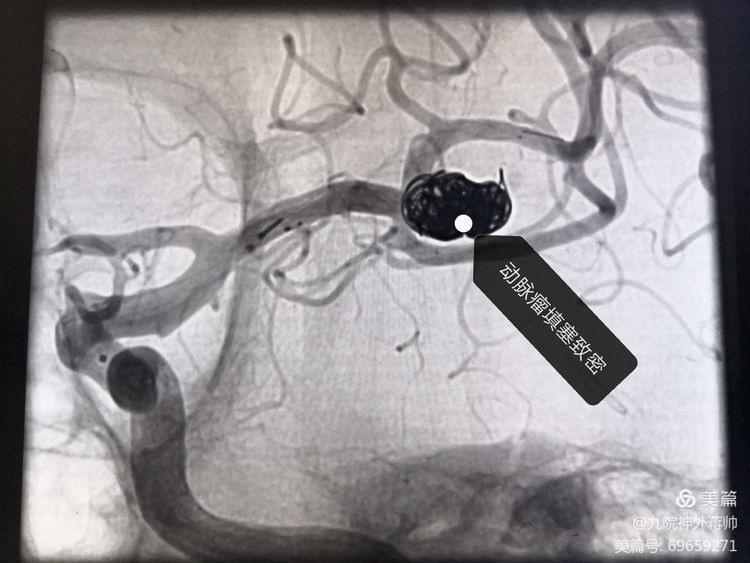

因动脉瘤复杂,单纯行动脉瘤栓塞难度很大,如需再植入支架,更是难上加难。刘展会主任结合患者病情,制定了详细的手术策略及应对措施。经过三个多小时的连续奋战,刘展会主任、张西安副主任医师、蒋帅医师联合为徐老师实施“支架辅助下左侧大脑中动脉动脉瘤介入栓塞术”,手术顺利。